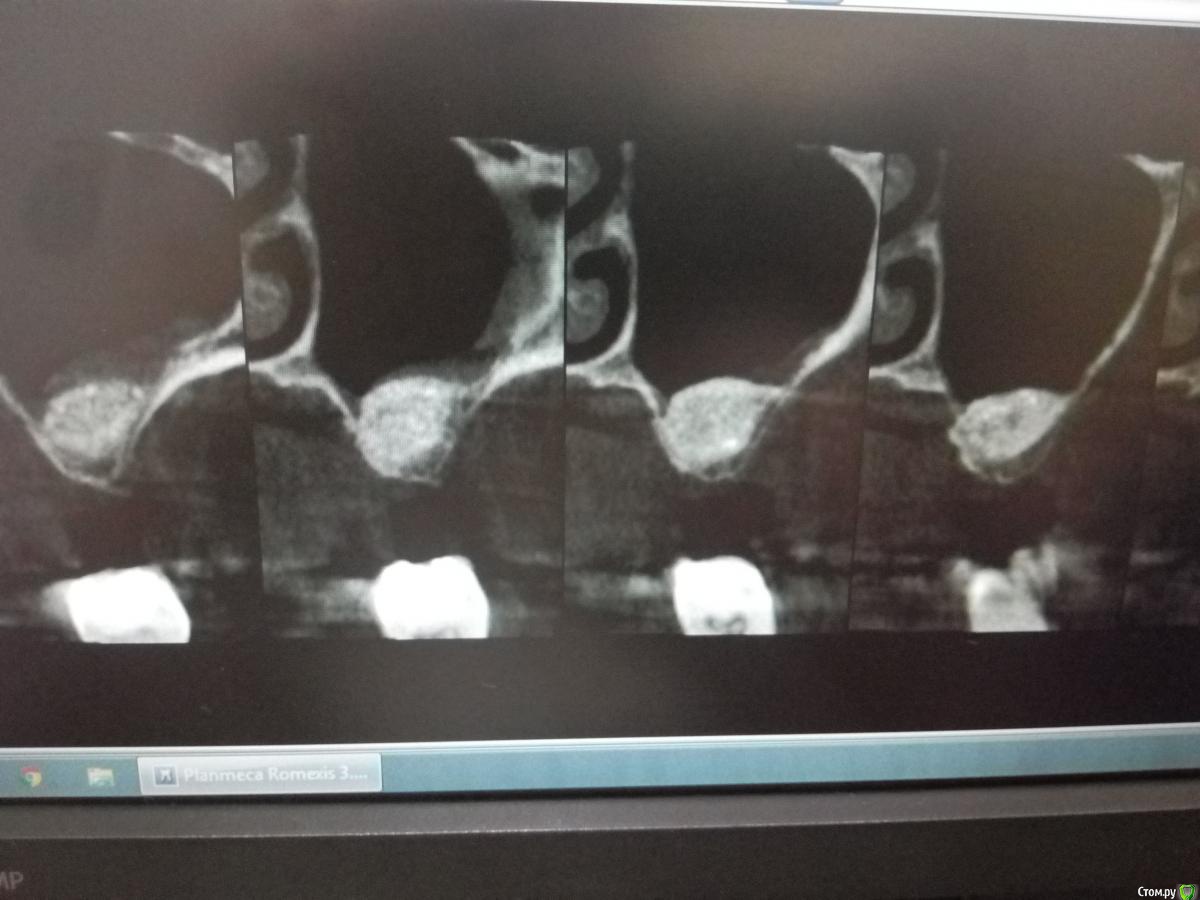

Sampson Опубликовано 14 августа, 2018 Поделиться Опубликовано 14 августа, 2018 (изменено) В феврале провел первый свой открытый синус.Снимок доПосле операцииНеделю назад пришла на контроль. Изменено 14 августа, 2018 пользователем Sampson Ссылка на комментарий